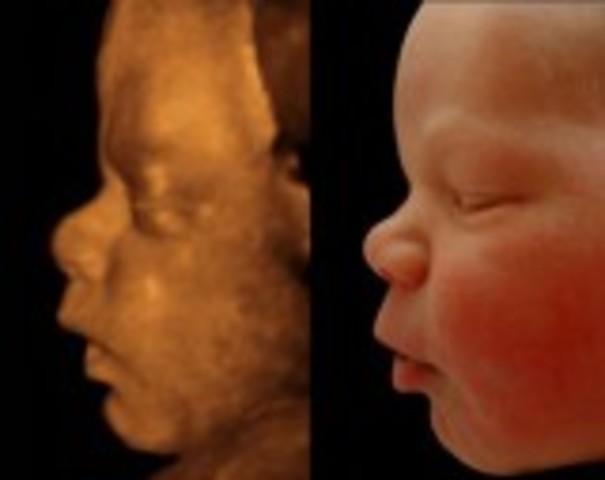

This is the start of the third trimester and the look of the baby will be the same at birth. The brain is rapidly growing, and the retina of the eyes are developing.

• Week 28

Week 28

The baby is now entering REM sleep and the eyelids can open now. If this baby was born prematurely they have a 90% chance of living.